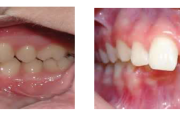

prognaatne hambumus, ülemised eeshambad on ettepoole alumiste suhtes ja eest

Normaalse jäävhammaskonna pilt küljelt ja eest vaadatuna.